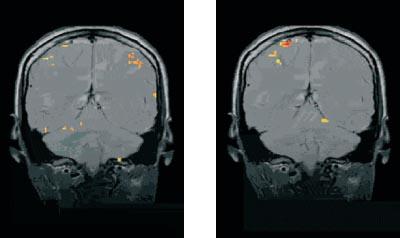

Hersenscans laten duidelijk verschil zien als iemand liegt of de waarheid spreekt, zo blijkt uit een voordracht op het jaarsymposium van de Radiological Society of North America dat begin december 2004 in Chicago werd gehouden.

Het onderzoek werd uitgevoerd met behulp van functionele MRI (fMRI). Dit is een gewone MRI…